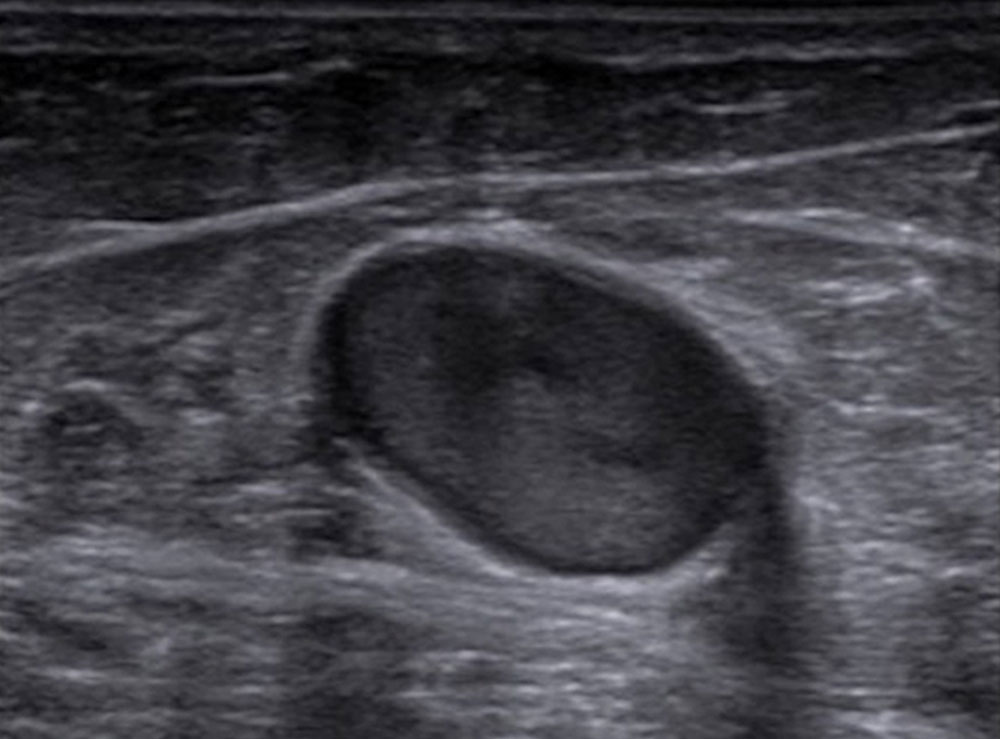

The most important imaging to detect or exclude phlebothrombosis is sonography. The affected vein section shows the thrombus contained in the vessel lumen, which cannot be compressed by compressing the vein with the transducer. Depending on age, this vascular thrombus tends to have a relatively low echogenicity initially in acute cases. The vein diameter is significantly increased by the intraluminal thrombus in the acute phase. In color-coded duplex sonography (CCDS), no color signal is found in the vein owing to the lack of blood flow, even at very low PRF settings (low pulse repetition frequency PRF = high detection sensitivity for flowing blood). With increasing thrombus age, the thrombus shrinks in size and becomes increasingly echogenic. In the further course, at least partial recanalization of the thrombosed vein occurs in favorable cases. Often beginning at the vein wall, blood (echo-free on ultrasound) again flows through the vessel surrounding the thrombus.